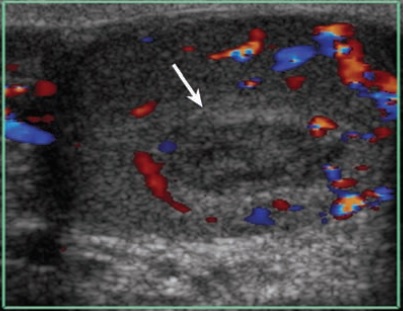

- Mất tưới máu trong tinh hoàn: vỡ tinh hoàn sẽ làm mất tưới máu một phần hay toàn bộ tinh hoàn tùy mức độ thương tổn (Hình6).. Đây là một dấu hiệu rất quan trọng giúp đánh giá khả năng sống của nhu mô tinh hoàn và quyết định phương pháp phẫu thuật. Mất tưới máu 1 vùng trong tinh hoàn có thể là thứ phát sau tụ máu trong tinh hoàn (Hình7).. Nếu vùng thiếu tưới máu lớn có thể phải phẫu thuật lấy khối máu tụ.

Hình 7.  Máu tụ trong tinh hoàn

* Nguồn: theo Bhatt S (2008) [2]